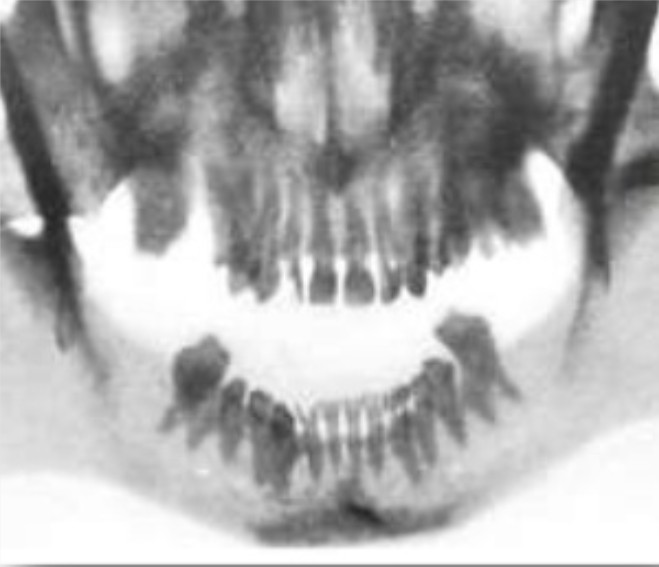

PERIAPICAL NIÑOS

Tamaño de 2 x 3.5 cm en niños

El estudio radiográfico de un niño tiene 10 radiografías

Centrales y laterales: vertical se toman los dos centrales y laterales en una radiografía =2 radiografías

Caninos: vertical una por cada Canino= 4 radiografías

Molares: horizontal, las dos molares en una radiografía, una por cuadrante= 4 radiografías